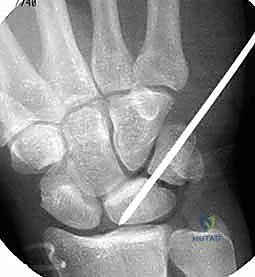

TECH FIG 6 • A. K-wire placed in triquetrum at a 45-degree angle.

TECH FIG 6 • B. K-wire advanced into lunate.

TECH FIG 6 • C. Second K-wire placed in lunotriquetral joint.

- K-Wire Placement: Once reduced, we need to temporarily stabilize the joint.

- First K-wire: Insert a 0.045-inch or 0.062-inch smooth K-wire into the triquetrum at approximately a 45-degree angle, aiming towards the lunate. Advance this wire across the lunotriquetral joint and into the lunate. Ensure good purchase in both bones.

- Second K-wire: Place a second K-wire across the lunotriquetral joint, ideally starting from the lunate and crossing into the triquetrum, or vice-versa, to provide rotational stability. This creates a more rigid construct.

- Fluoroscopic Confirmation: Use intraoperative fluoroscopy to confirm anatomical reduction and optimal K-wire placement. Check both AP and lateral views. Ensure the wires are not impinging on articular surfaces or neurovascular structures.